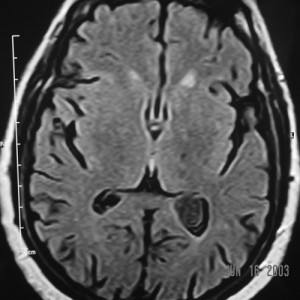

The images are a combination of T1 (before and after gadolinium enhancement), T2, and FLAIR pulse sequences in axial, sagittal and coronal sections of the patient’s brain (not all of the original images are in the monograph).

They reveal a 2cm mass in the trigone of the left lateral ventricle, centered within the choroid plexus. It has intermediate signal intensity on the pre-gadolinium T1WI, is hyperintense on the T2WI and enhances intensely and homogeneously after intravenous gadolinium administration. The mass is round, well-defined, has no mass-effects and does not invade the brain parenchyma. The ventricles are not dilated. The remainder of the brain is normal.